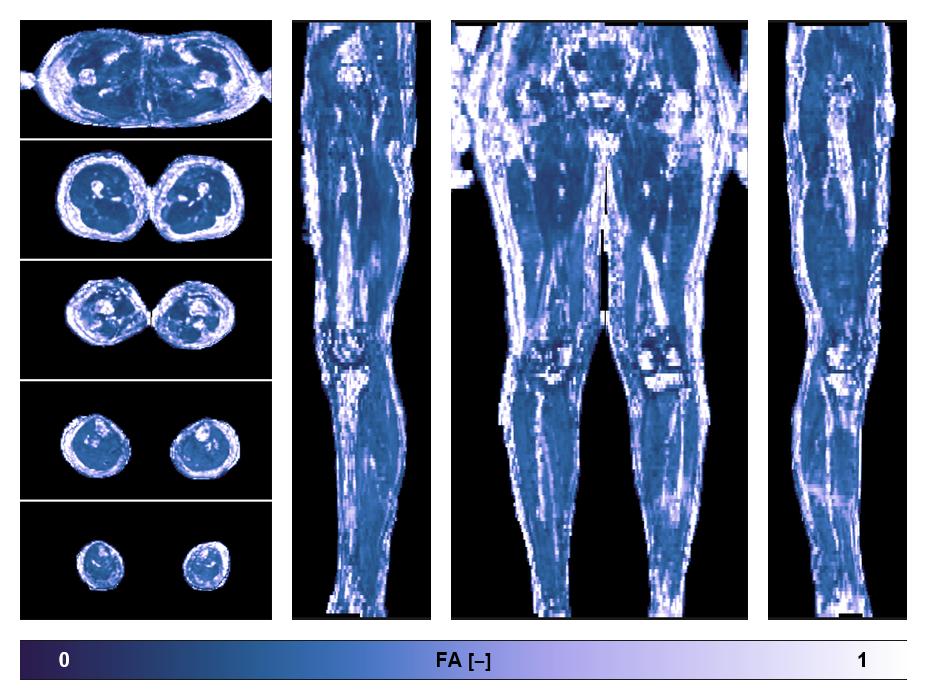

• Fractional anisotropy

IVIM corrected whole leg muscle fractional anisotropy obtained from diffusion tensor imaging.